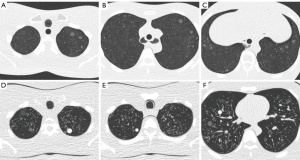

The LSCT001 phantom was scanned using two 64-row multi-detector CT scanners: Brilliance 64 and IQon Spectral CT (Philips Healthcare, Eindhoven, The Netherlands). Images were acquired using two different radiation dose levels, with a collimated detector width of 64×0.625 mm, a tube voltage of 120 kVp, and a maximal tube current-time product of 30 or 15 mAs. In consideration of the interscan variability, each scan was repeated 30 times. The scans were reconstructed with a slice thickness of 1 mm and an increment of 1 mm, as recommended in lung cancer screening guidelines (10,11). Images from Brilliance 64 were reconstructed by two methods: filtered back projection (FBP) and iterative reconstruction (IR) (iDose4 level 5, Philips Healthcare, Eindhoven, The Netherlands). Images acquired by IQon Spectral CT were reconstructed with a dedicated spectral IR algorithm (Spectral Level 5, Philips Healthcare, Eindhoven, The Netherlands).

The Lungman phantom was scanned using a 256-channel multi-detector CT scanner (Philips Healthcare, Eindhoven, The Netherlands). Images from the iCT 256 were acquired with a collimated detector width of 128×0.625 mm, a tube voltage of 120 kVp, and a maximal tube current-time product of 30 mAs. The CT scan was repeated 19 times. The scans were reconstructed by FBP and iterative model reconstruction (IMR) (IMR level 2, Philips Healthcare, Eindhoven, The Netherlands) using a slice thickness of 1 mm with an increment of 1 mm.

For nodule segmentation, a commercially available software program, LuCAS (Monitor Corporation, Seoul, Korea), was used. LuCAS is a deep learning-based computer-aided diagnosis (DL-CAD) solution that provides detection and segmentation applications for pulmonary nodules. After loading the DICOM images into the software, the software detected nodules and initiated the segmentation (Figure 3). Nodule volume and diameter were quantified in a fully automatic manner.